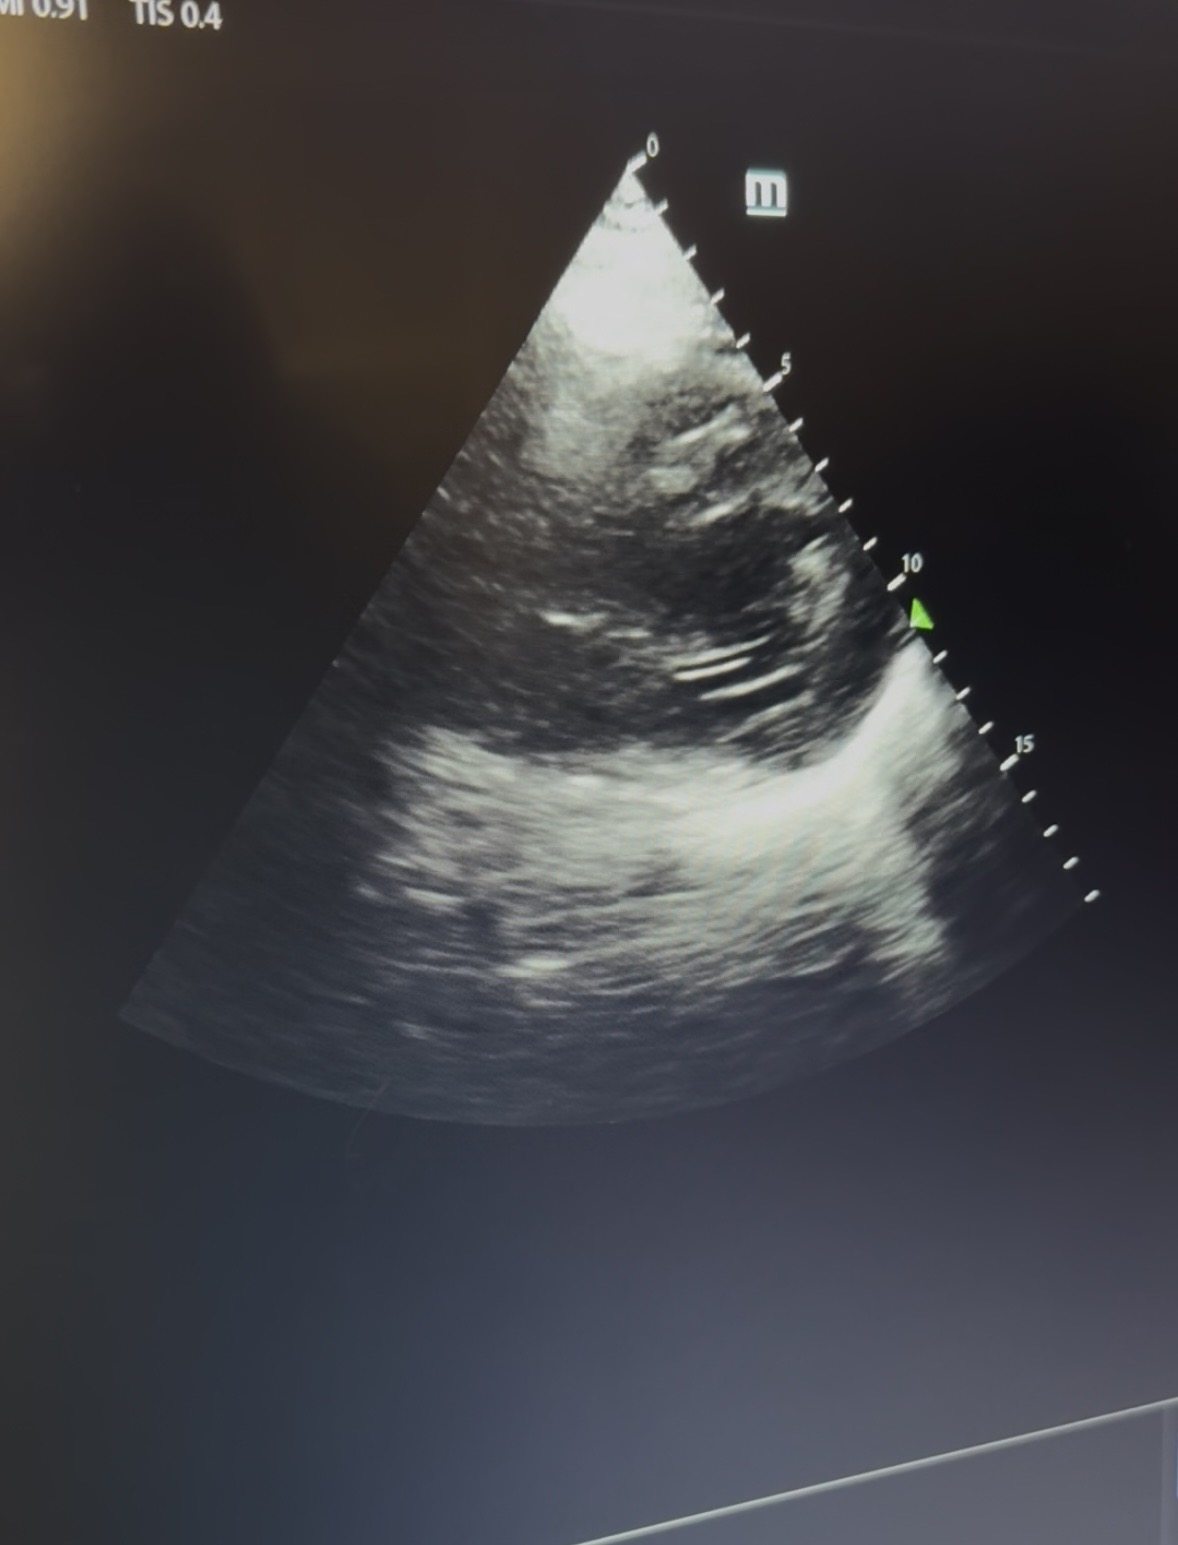

Se solicita analítica sanguínea completa, angio-TC pulomnar tras esta y se realiza ecocardiografía a pie de cama.

Resultado de pruebas complementarias: AS: fracaso renal agudo; angio-TC: normal; Ecocardiograma: HVI concéntrica. Hipocinesia global leve con FEVI en torno al 45%. Dilatación auricular izquierda. Válvula mitral engrosada con movimiento restrictivo e IM II/IV.

Impresiona por lo tanto de una emergencia hipertensiva con EAP secundario a cardiopatía hipertensiva. FEVI 45%. Fracaso renal agudo por EAP / emergencia hipertensiva.

La ecografía se trata de una herramienta diagnóstica inmediata de la disnea aguda. En concreto la ecocardiografía, nos permite la detección precoz de daño por hipertensión. Mejorando, por tanto, la toma de decisiones del médico de Familia, así como pudiendo realizar un seguimiento adecuado del paciente.